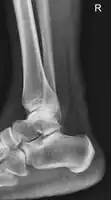

Achilles tendon (a commonly affected tendon)